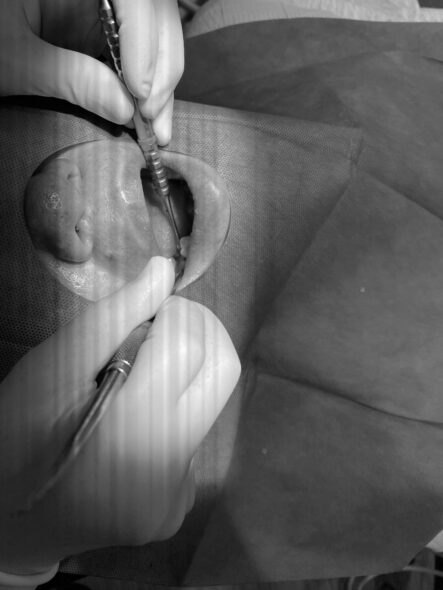

右下7番インプラント1次オペ

さて本日インプラント埋入オペが行われました。

下記がオペの様子です。

こちらの患者様は右下のブリッジがしみるとのことでブリッジを外して

検査をおこなったところ状態が悪く抜歯となりインプラント治療を選択されました。